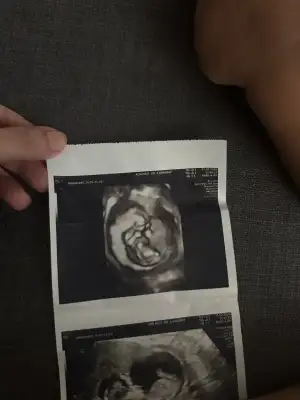

Kızlar dün doktorum cinsiyet tahmini yaptı kız büyük ihtimal ama 3 hafta sonra tekrar bakarız kesin o zaman belli olur dedi ben hep erkek hissediyordum ama kız olunca çok mutlu oldum hissiyat olarak sadece erkek olucak kesin diyordum ama yanıldım sanırım sizce cinsiyeti değişicek mi çok heycanlıyım ☺️ Ultrason fotoğrafını asağıya ekliyorum Eki Görüntüle 3233482 12 iç haftada %99 erkek dedi doktor sizcede erkekmi ?

Doktorumuz 12 iç haftada önce emin olamadı sonra %99 erkek dedi bide siz değerlendirirmisin , böyle olup sonradan değişenler varmış şuan 13 haftalığız acaba tekrar emin olmak için baktırsammı ?